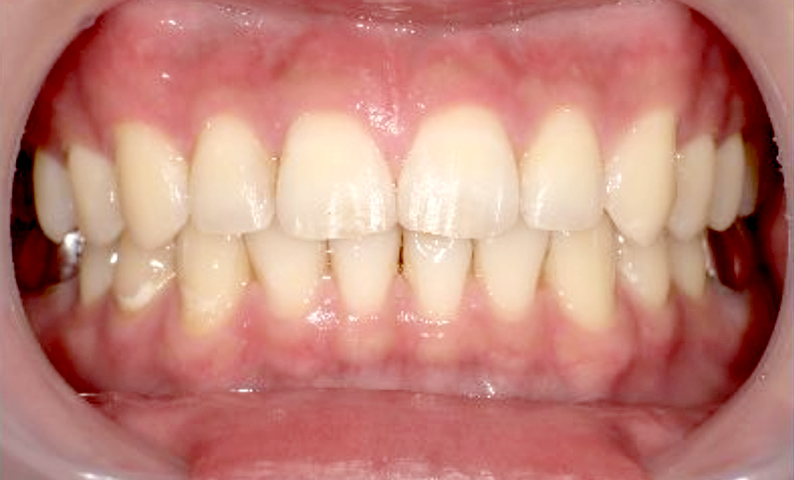

| 治療前 | 治療後 |

|---|---|

|